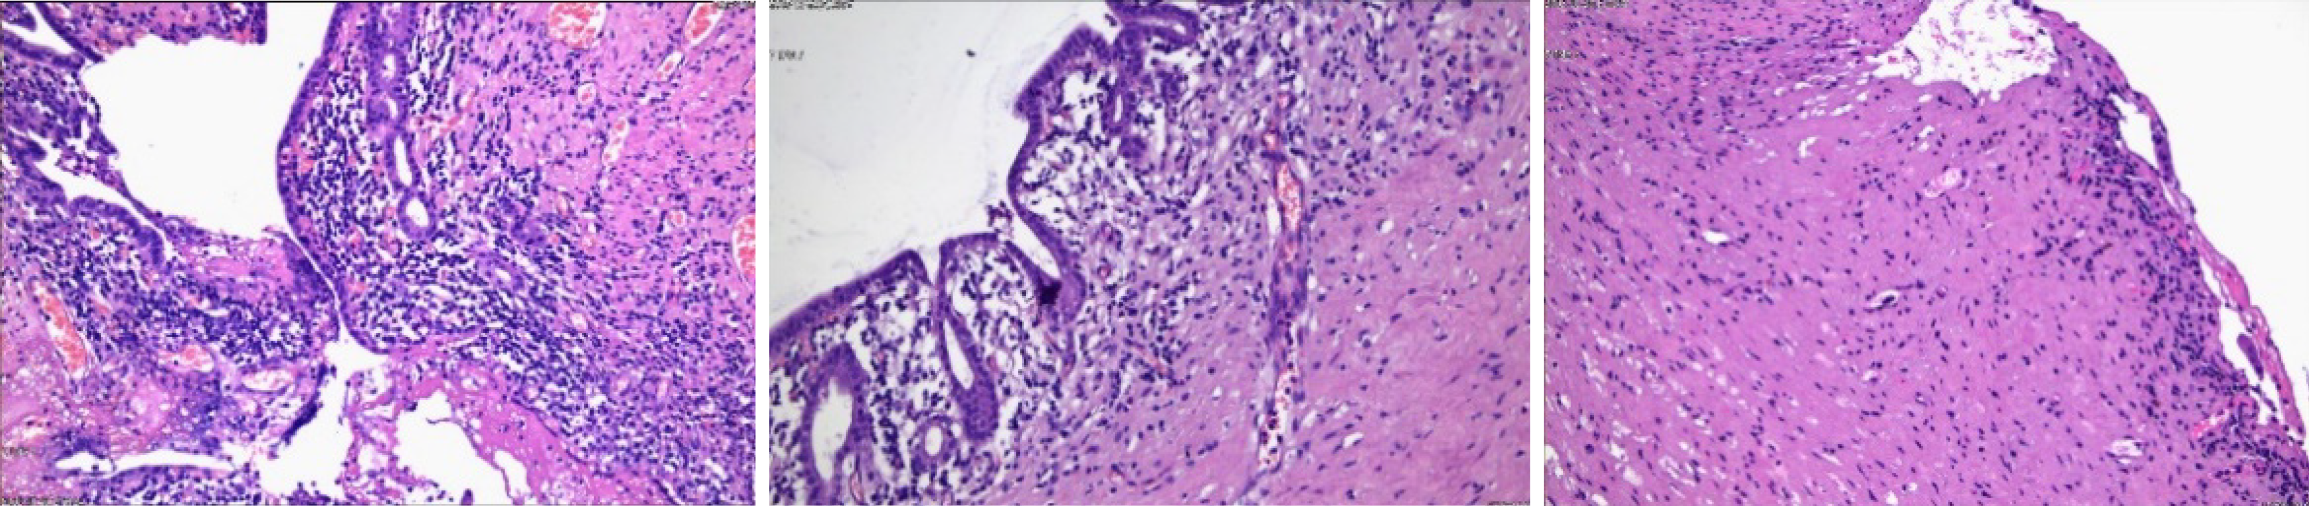

Six months later, the patient was readmitted for surgical treatment, and received a follow-up abdominal CT and MR abdominal scan + MRCP, which confirmed significant reduction in cyst expansion and hydronephrosis resolution (Figure 4). Laboratory parameters were within normal range (Table 3). Following a further clinical evaluation, the patient was deemed fit for surgery. Therefore, a comprehensive preoperative preparation was conducted, followed by cystectomy and Roux-en-Y hepaticojejunostomy through a laparoscopic approach. Postoperatively, the patient continued receiving antibiotics, fluid therapy, nutritional support, and treatment to maintain electrolyte and acid-base balance. On the first postoperative day, moderate ambulation was recommended to promote gastrointestinal function recovery. On the second day, the patient’s gastrointestinal tract became functional, and soft food was introduced. The patient did not report any discomforts. Postoperative pain was managed with opioid analgesics, which achieved good pain control. Details of the pathological findings on the surgical specimen are presented in the table below (Figure 5).